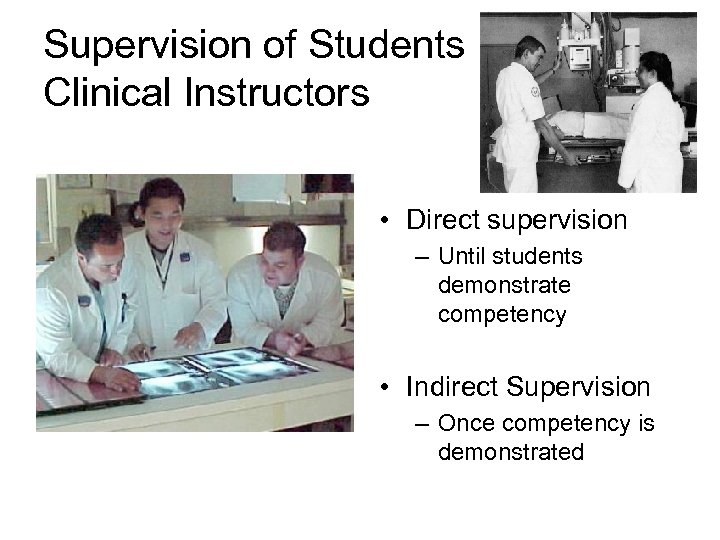

Supervision of Students Clinical Instructors • Direct supervision – Until students demonstrate competency • Indirect Supervision – Once competency is demonstrated

Supervision of Students Clinical Instructors • Direct supervision – Until students demonstrate competency • Indirect Supervision – Once competency is demonstrated